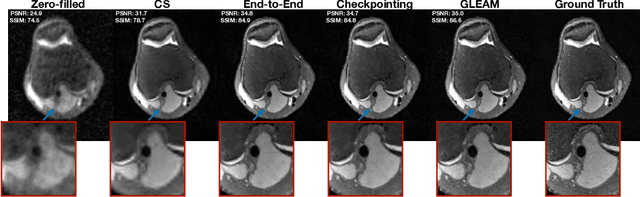

Abstract:Unrolled neural networks have recently achieved state-of-the-art accelerated MRI reconstruction. These networks unroll iterative optimization algorithms by alternating between physics-based consistency and neural-network based regularization. However, they require several iterations of a large neural network to handle high-dimensional imaging tasks such as 3D MRI. This limits traditional training algorithms based on backpropagation due to prohibitively large memory and compute requirements for calculating gradients and storing intermediate activations. To address this challenge, we propose Greedy LEarning for Accelerated MRI (GLEAM) reconstruction, an efficient training strategy for high-dimensional imaging settings. GLEAM splits the end-to-end network into decoupled network modules. Each module is optimized in a greedy manner with decoupled gradient updates, reducing the memory footprint during training. We show that the decoupled gradient updates can be performed in parallel on multiple graphical processing units (GPUs) to further reduce training time. We present experiments with 2D and 3D datasets including multi-coil knee, brain, and dynamic cardiac cine MRI. We observe that: i) GLEAM generalizes as well as state-of-the-art memory-efficient baselines such as gradient checkpointing and invertible networks with the same memory footprint, but with 1.3x faster training; ii) for the same memory footprint, GLEAM yields 1.1dB PSNR gain in 2D and 1.8 dB in 3D over end-to-end baselines.